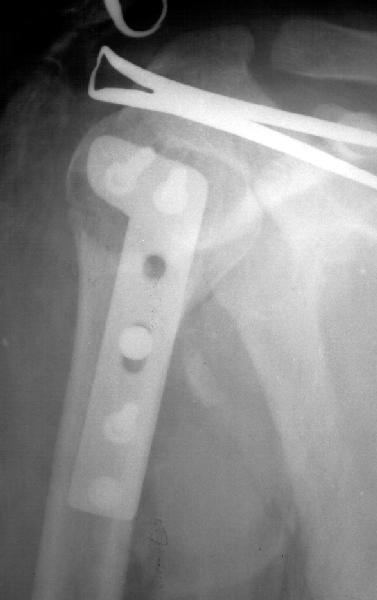

Мужчина 25 лет 16 августа 2002 г. в автоаварии получил перелом шейки плеча (снимок 1); 5 сентября в городской больнице выполнен остеосинтез пластинкой (снимок 2).К настоящему времени попал к нам на разработку ввиду выраженной контрактуры плечевого сустава. В течение последнего месяца беспокоят умеренные боли в области плечевого сустава, усиливающиеся при разработке, еще и торчит край пластинки. Нынешняя рентгенологическаякартина на снимках 3 и 4. Головка плеча уменьшается, сращение сомнительное.Кроме удаления пластинки, что еще на сегодня целесообразно сделать?Заранее спасибо.

I think the AVN is at least stage 3 with deformity of the head. I would advise a removal of implant and a cementless humeral head replacement. Or if you have the experience and the implant, as well as adequate bone stock, maybe a resurfacing prosthesis like the Copeland shoulder. I am not sure if you can do it one or two stages. You can perhaps do it in one stage if there is no sign of infection and if the patient condition allows it. You should not worry too much about age since this is a non

The current xrays indicate failure of the implant with losening. I would make sure there was no evidence of infection ( exam,ESR,CRP etc.) . I would agree with implant removal . I think this would be a suitable case for a circular ring fixator and compression, either a standard IIizarov or Taylor Spatial frame would be appropriate. I note from your previous cases that you have a high level of experience with this method.

Думаю, что надо удалять железо с одновременной ревизией ротаторной манжеты и субакромиального пространства. При необходимости - акромиопластика. А вообще, прогноз сомнительный. На западе в конечном итоге такое кончается эндопротезированием.